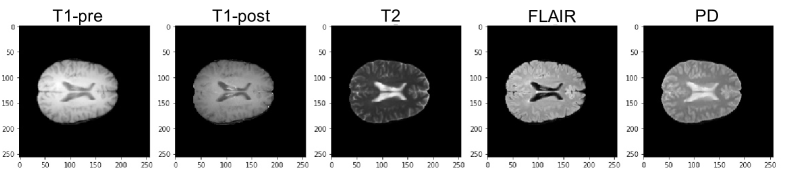

Brain MRI. We obtain a total of 360 MRI images for all 300 patients. All imaging studies were performed on a Philips 3.0T Ingenia scanner (Philips Medical Systems, Best, Netherlands). Some patients can have multiple MRIs from different clinic visits. The MRIs include five sequences: pre-contrast and post-contrast T1-weighted sequences (T1-pre, T1-post), T2-weighted sequences, proton density-weighted sequences (PD) and fluid-attenuated inversion recovery sequences (FLAIR). All sequences were acquired with a field of view of 256 mm x 256 mm x 44 mm. For each patient, the MRI images were acquired in the axial plane. Figure 3 displays the MRI sequences of a sample patient. All MRI sequences are skull-stripped using Simple Skull Stripping (S3) [26] and the SRI24 template [27], bias-corrected using N4 Bias Field Correction to adjust the low-frequency intensity [28], and co-registered using FreeSurfer [29] to a common template (SRI24).

Refer to caption

Figure 3: The MRI sequences of a patient as an example.